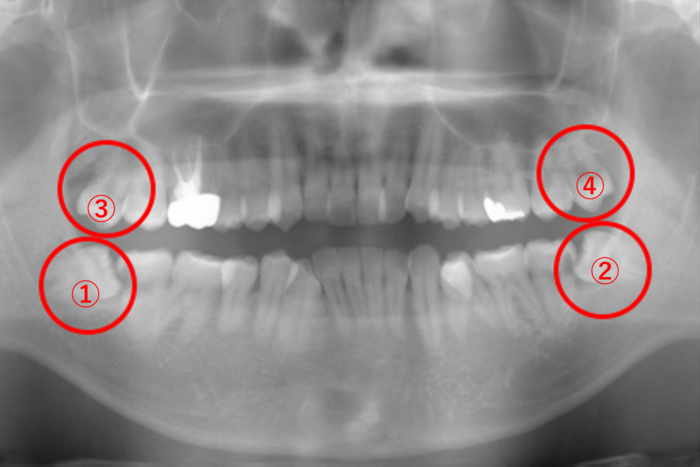

| 年齢・性別 | 26歳・男性 |

|---|---|

| 主訴 | 左上の親知らず(画像④)が痛くて我慢ができない。どちらかというと鋭い痛みがある。 |

| 歯ブラシ | 奥まで磨けていない。お口の中に汚れが結構残っている。 このままでは親知らずだけではなく、他の歯が虫歯になる可能性が高い。 |

親知らずが生えることによる痛みとは異なる「鋭い痛み」の原因究明のため、まずはレントゲンを撮影しました。

画像④の親知らずに大きな黒い虫歯の影が見えます。虫歯になると歯が溶けて柔らかくなるので、レントゲンには黒く写ります。

また、1番奥にある親知らずまで歯ブラシが届かずに、気付いたら虫歯が大きくなっていたことが予想されます。

虫歯の痛みが強い時に親知らずを抜こうとしても麻酔が効きにくいことが予想され、患者さまの負担を考えると無理に親知らずを抜かないことも選択肢のひとつになります。

そこで、この患者さまには、今すぐに親知らずを抜くのではなく、まずは虫歯の痛みをとる治療を優先させて、虫歯の痛みが無くなってから親知らずを抜きましょうと説明しました。

画像④の親知らずを抜いた場合、下の➁の親知らずを抜かずに放置すると上に伸びて来て、かみ合わせの邪魔をすることがあります。

そのため、上下同時に親知らずを抜くか、④の親知らずを抜いてから➁の親知らずを抜くか、どちらかになります。また、右上④の親知らずがないため、②と④の抜歯後、①の親知らずを抜きます。

上下どちらかの親知らずを抜歯した場合、その対合する親知らずが生えていたら抜歯し、片側の親知らずを抜歯した場合は、もう片側上下にある親知らずを順次抜くことを検討するとその後のトラブルは少ないと思います。

今後、画像➁の親知らず周りも腫れることが予想され、同じように噛んで出血するというパターンも考えられるため、できれば4本とも抜いた方が良いでしょう。

初回は、止血処置、抗生剤の投与と服用で腫れを引かせ、後日、画像①の親知らずを抜きました。